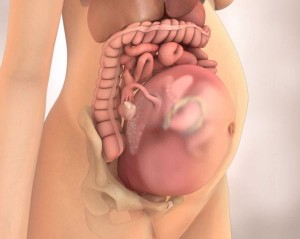

Органи жінка на 32-му тижні вагітності

Розмір живота жінки на 32-му тижні вагітності

Через своїх розмірів малюк провокує збільшення матки. Матка починає сильно здавлювати внутрішні органи і, зокрема, нижню порожнисту вену. Через це лікарі забороняють вагітній жінці лежати на спині. У положенні лежачи плід тисне на порожнисту вену, викликаючи порушення кровопостачання організму матері.

Внутрішньоутробний розвиток дитини на 32 тижні

Візуалізація малюка на 32 тижні вагітності

3D візуалізація дитини на 34 тижні вагітності